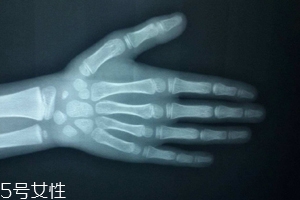

只需要拍一張左手正位片。

拍攝時,左手五指自然張開,手心向下,中指與前臂保持中一條直線(盡量不要左右偏,手臂放平不要上抬),X線球管對準(zhǔn)第三掌骨頭,球管與X光片距離在80CM左右。